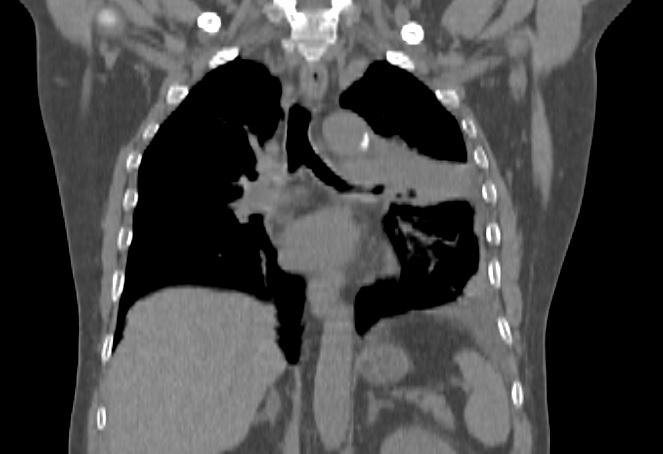

Pacientul M.L. in varsta de 56 ani, fumator de 40 ani, 20PA, s-a prezentat in clinica noastra pe data de 30.11.2022, cu diagnosticul de adenocarcinom pulmonar (neoplasm pulmonar) la nivelul lobului pulmonar superior stang, o tumora in stadiul IIIC, de dimensiuni mari T3, cu invazie ganglionara si mediastinala. Cazul a fost prezentat in Comisia Oncologica Multidisciplinara a clinicii noastre, unde s-a decis initierea tratamentului oncologic. Tumora fiind avansata loco-regional, era exclusa interventia chirurgicala in acest stadiu de boala (cancer pulmonar inoperabil).

Astfel, in perioada 5.12.2022 – 26.01.2023, pacientul a efectuat radioterapie externa cu fotoni, tehnica VMAT-CBCT, pana la doza totala DT = 66 GY/volum tinta formatiune tumorala pulmonara, un numar total de 33 fractii, concomitent cu administrarea saptamanala de polichimioterapie de radiosensibilizare, cu toleranta foarte buna.

Prezentam acest caz la scurt timp dupa finalizarea tratamentului (tratament cancer pulmonar), deoarece acesta este un caz fericit, la care s-a observat un raspuns aproape total chiar din timpul tratamentului RT, imaginile CBCT efectuate la inceputul, in timpul si la finalul tratamentului RT, pe care le atasam, aratand clar un raspuns extraordinar de bun la tratamentul efectuat.